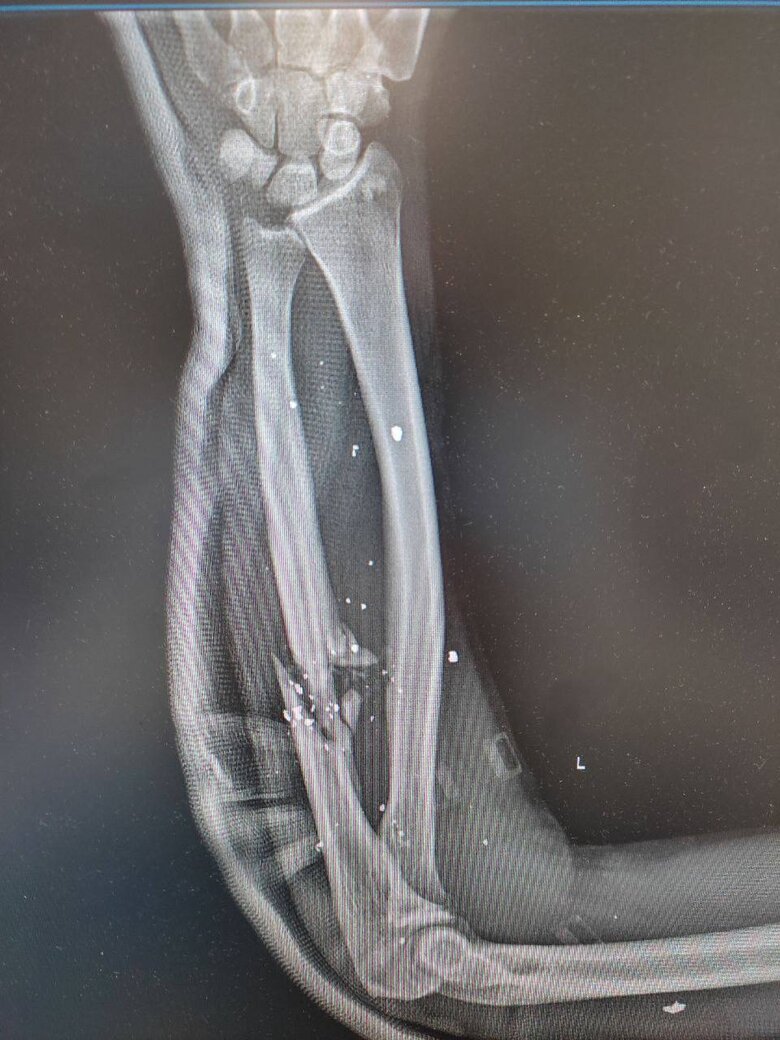

- Ні. Сухий закон. Я завжди їм кажу: "Ви – честь українського народу!". Якщо військовий дозволяє собі перебувати десь у стані алкогольного сп’яніння, так його й сприйматимуть. А я хочу, щоб в Україні було таке ставлення до військовослужбовців: це люди, які віддали своє здоров’я, життя за те, щоб українці жили далі на своїй землі. Це приклад! Тому й поведінка має бути відповідною, щоб не відбувалося знецінення того, що ми робимо. Для мене важливо, що про нас думають. Я віддаю війні всього себе. У мене двоє дітей. Я зараз на третій групі інвалідності. В мені – мінімум 130 уламків (це ті, які можна порахувати)...

- Можна піти на МРТ, щоб витягти всі уламки за один раз – магнітом (сміється. – О.М.). На жаль, цього неможливо зробити. Вони вже на все життя. Якщо подивитися мій рентген – там усе біле. У мене ось не вистачало три сантиметри кістки (показує ліву руку, яка вся в шрамах. – О.М.) – вирвало.